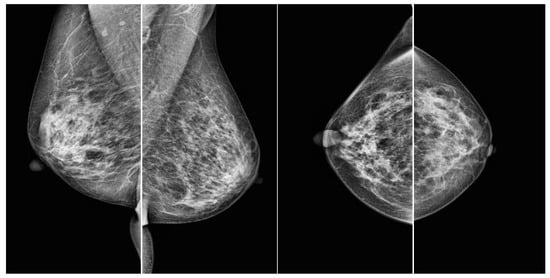

Therefore, this study tested the hypothesis that prediction accuracy improves when images are classified based on whether or not they have annotated mask information for regions of interest, with subsequent separate training and prediction for each of the four mammographic views (RCC, LCC, RMLO, LMLO), before merging the results. A standard mammographic examination typically includes four views: the left mediolateral oblique view (LMLO), right mediolateral oblique view (RMLO), left craniocaudal view (LCC), and right craniocaudal view (RCC) (Figure 1).

Figure 1. Samples of four views from a mammography from VinDr [22]. From left to right: LMLO, RMLO, LCC, and RCC.